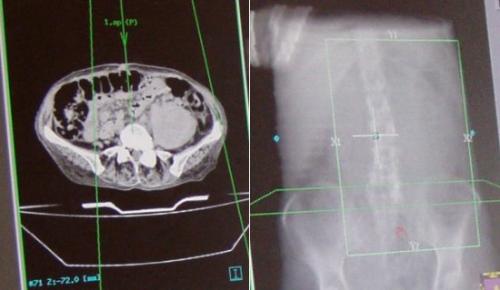

Wat tegenwordig niet meer los van elkaar gezien kan worden is de rol die de medical imaging (MI) speelt in de radiotherapie. Je hebt het dan over de radiodiagnostiek. Alle behandelingsplannen en berekeningen zijn gebaseerd op de beelden die we krijgen uit MRI-scans en CT-scans. De apparaten voor de behandelingen zijn meestal een combinatie van een versneller en een scan apparaat. Binnen het UMC zijn er verschillende ontwikkelgroepen die zoeken naar wat we ermee kunnen binnen de radiotherapie. De ontwikkeling van MRI is belangrijk als middel om tot betere behandelingsplannen te komen.

Met de computer wordt de beste combinatie van stralingsrichting bepaald.